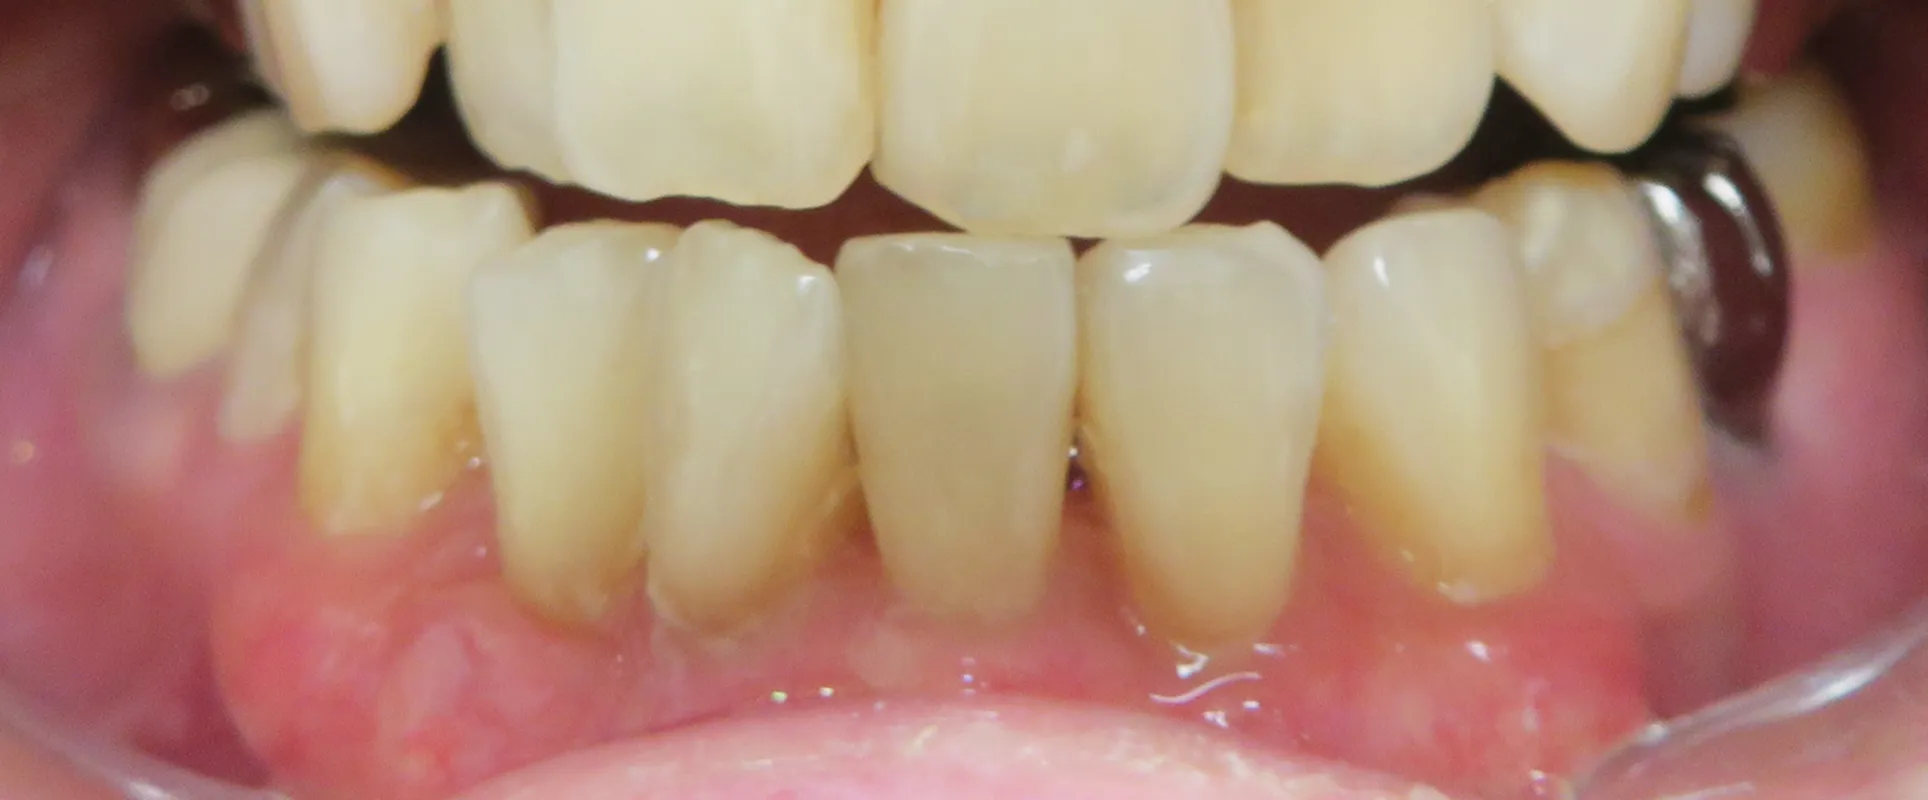

歯肉再生PRP注射の症例写真

BEFORE

AFTER

施術名:PRP注射/料金の目安:上前歯または下前歯 8本 89,000円(税込 97,900円)/施術の副作用リスク:効果の個人差、腫れ、左右差、内出血、ふくらみ、しこり、アレルギー

40代 女性

下前歯(8本)の歯茎に注入

施術前は歯茎が退縮し、歯根が露出している状態で、歯が長く見えていましたが、治療後は歯茎に厚みが増し、歯と歯茎のバランスが改善しました。

あわせて、歯茎の色調も改善し、より自然で若々しい印象となっています。

※効果には個人差があります。